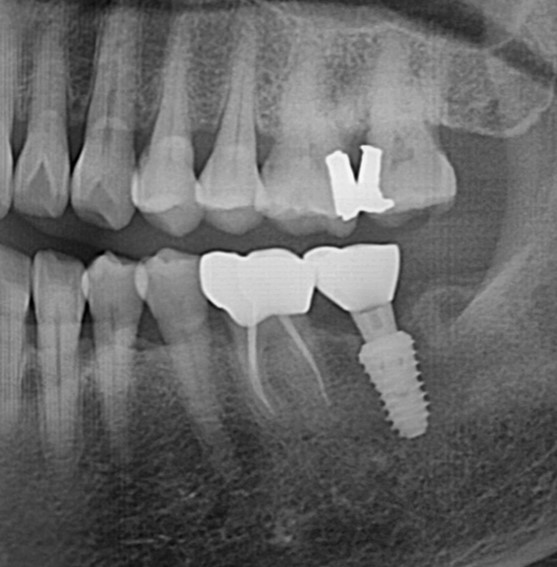

재신경치료사례

전후사진